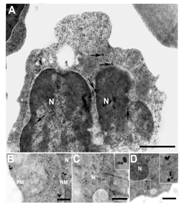

Figure on the left: (A) Caveolin-1 localization in rat PMNs by immunoelectron microscopy, showing caveolin-1 immunolabeling. (B) Caveolin-1 immunolabeling in the nucleus, nuclear membrane and in the plasma membrane (C) Colocalization of iNOS (15 nm) with caveolin-1 (10 nm) in the nucleus and (D) cytoplasm. Bars represent 100 nm (A) and 100 mm (B-D). Figure on the right: (A) iNOS immunolabeling (i), nucleus (blue) (ii), iNOS (red) (iii), caveolin-1 (green) (iv), merge of ii and iii (v) negative control with preimmunized sera (B) nNOS immunolabeling (i), nucleus (blue) (ii), nNOS (red) (iii), caveolin-1 (green) (iv), merge of ii and iii (v) negative control with preimmunized sera. Bar represent 5 μm (A, B). (C) NOS enzyme activity in cytosolic fraction (CF) and nuclear fraction (NF) of PMNs. Addition of CaM augmented NOS activity.